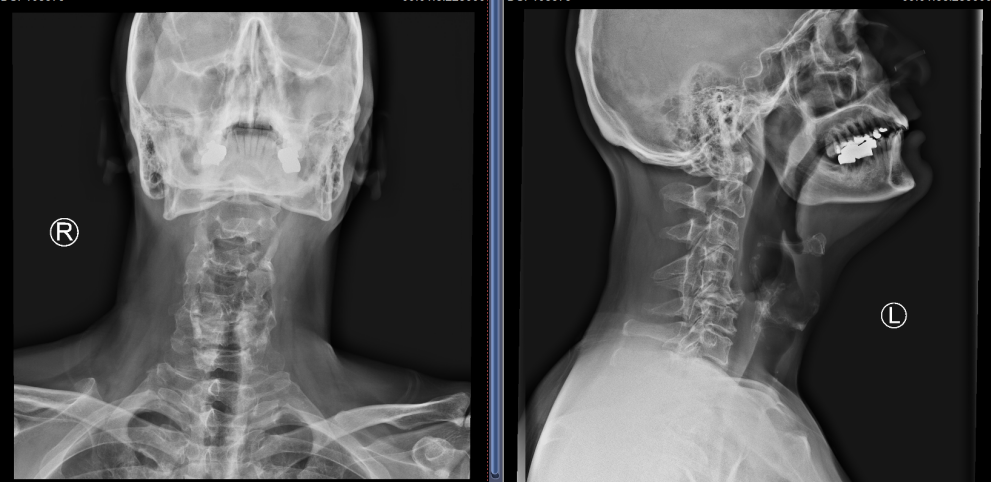

C5/6、C6/7椎间盘突出明显,椎管狭窄,脊髓受压严重

就这样,2022年3月,Hester办理了住院手续,在进一步的详细评估后,姜主任制定了经前路减压融合术的手术方案。与后路椎管扩大成型术相比较,具有创伤小、直接减压与恢复快的优点。但由于Hester颈椎的先天畸形与严重的骨质增生,手术难度却增加了很多。手术当天,在麻醉科医生黎鹏与手术室护士的密切配合下,姜为民主任带领王喜安副主任和赵星毅博士,经过两个多小时的精雕细琢,将增生的骨赘在狭窄变形的椎间隙里一一切除,解放了受压的脊髓,完成了这台特殊的“颈椎前路椎间盘切除+椎间融合术”。Hester在术后第一天就激动地告诉姜主任:“Right after the surgery I found the balance problem was gone. I can stand again on one leg without crashing on the floor now and the numbness in the finger is reduced.”(我右手持续了3年之久的麻木感已经明显缓解,佩戴颈托后试着下床行走,发现术前那种失去平衡的症状不见了,甚至单足站立也不怕摔倒)。

术后复查X片,C5/6和C6/7椎间隙高度恢复满意